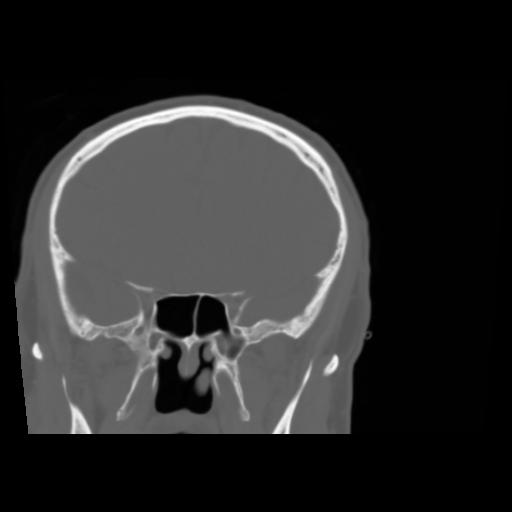

5 CEREBRO,,Coronal,3.000,CEREBRO,Coronal,